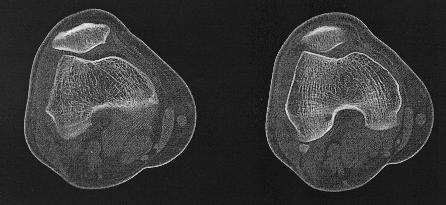

Een Ct-scan van het skelet wordt uitgevoerd wanner er een verdere

evaluatie nodigs van een lestel dat gezien is op een klasieke foto.

Denk aan fracturen, luxaties e.d., maar ook aan metastasen,

arthrose,...Zo kan het bijvoorbeeld zijn dat een letsle niet duidelijk

genoeg voorkomt op de foto's endat er dus twijfel bestaat. Maar ook kan

het zijn dat een CT-scan noodzaklijk is om een duidelijk beeld te

verkrijgen van een uitgebreide fractuur, om verder behandeling te

bepalen.